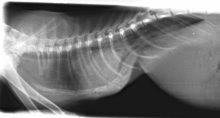

Chest Wall Deformities in Kittens (Pectus Excavatum)

Pectus Excavatum in Kittens Pectus Excavatum is a deformity of the chest wall where the caudal sternum deviates dorsally, ...